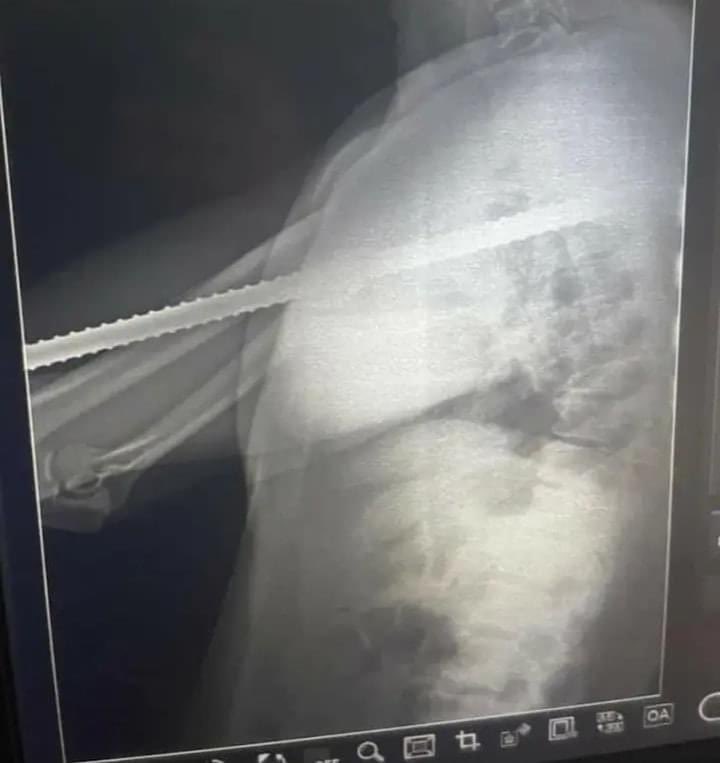

عامل بناء جاء للطوارئ بمستشفى القصر العيني بعدما أصابته سيخة وإخترقت صدره وخرجت بالجانب الآخر ..

ومن رحمة ربنا سبحانه وتعالى بيه إنو السيخة مرّت مابين القلب والرئتين والشرايين الرئوية والشريان الأورطي "الضخم" بدون ترك أي أثر او حتى جرح لجدران الأوعية الدموية ..

علماً بإنو ثُقب صغير في الشريان الأورطي الضخم ذا التدفق الدموي العالي ڪفيل خلال ثواني معدودة بقتل المُصاب من فرط النزيف ..

فلو قرر جراح ماهر إدخال سيخة بنفس المسار بدون قتل المُصاب لإحتاج لملايين الصور المقطعية والرنين الميغناطيسي وإجراء جراحة إستڪشافية

ولڪنها قدرة ﷲ تبارك وتعالى في النجاة بطريقة مُذهلة ..